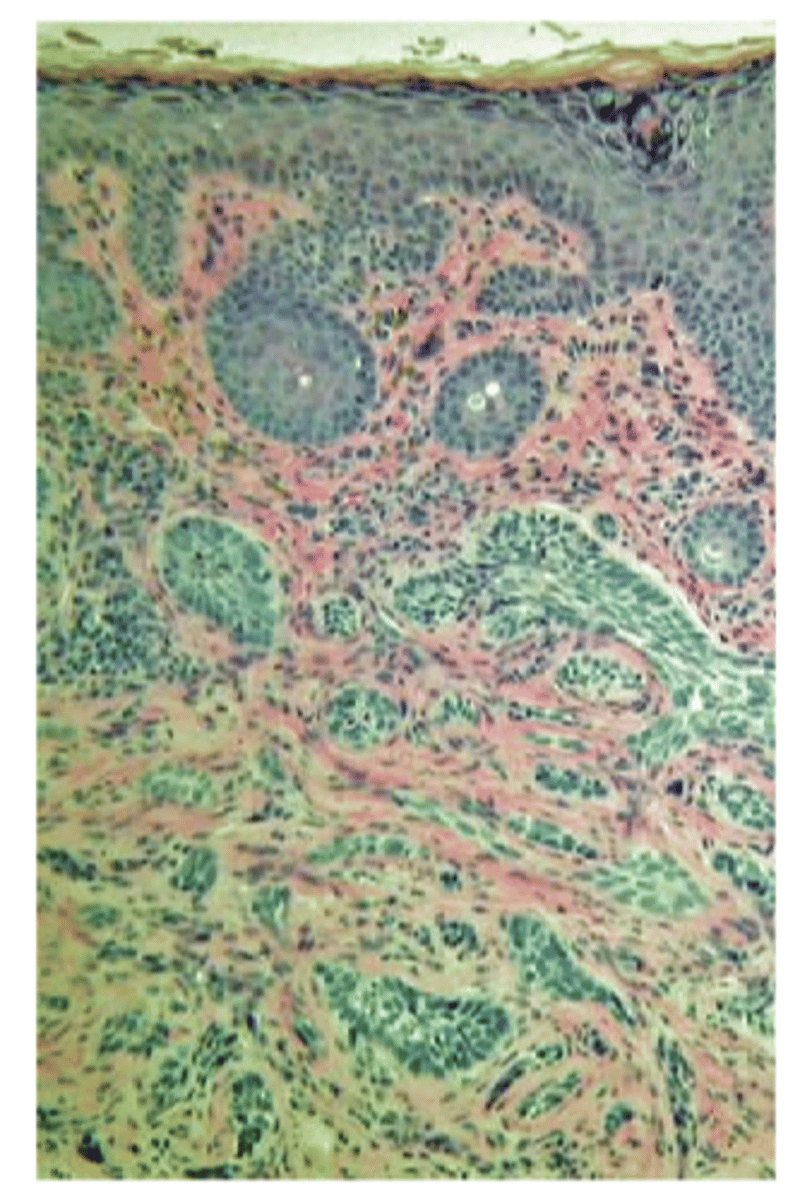

What is the histology behind BCC?

proliferation of epidermal basal cells that form tumor tissue in the form of:

strands

chords

islands packed with dense fibrous tissue seen in morpheaform (can be challenging to get full excision)